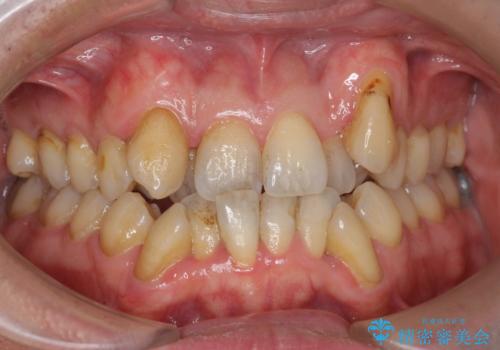

- 歯の色が茶色く気になっていると来院されました。

クリーニングとオフィスホワイトニングをおすすめしました。

オフィスホワイトニング(エクセレント)

歯が白く口元が明る爽やかなイメージになり、

大変満足していただけました。